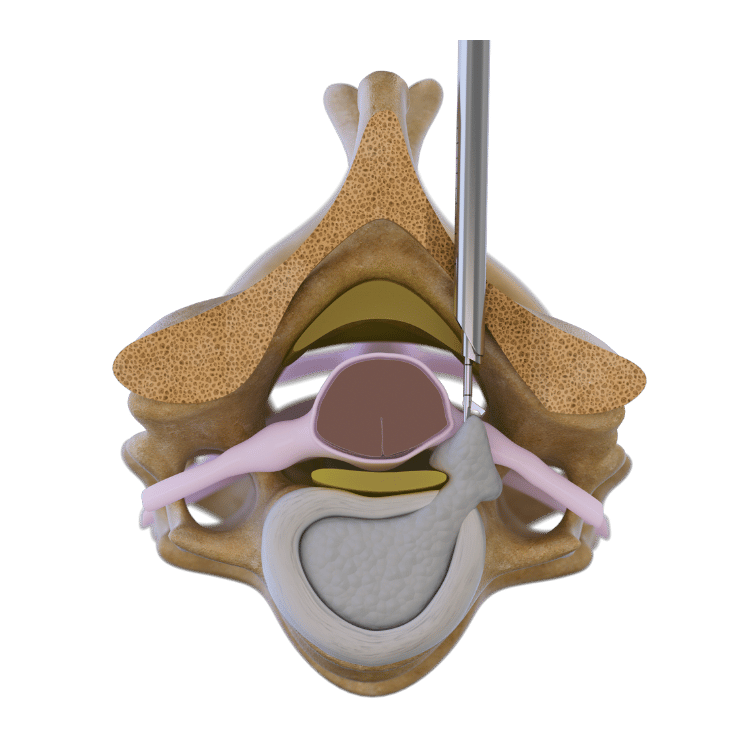

Interlaminar technique

The interlaminar technique accesses the spinal canal through the interlaminar window. This is usually possible at the L5/S1 level without additional bone material removal. In higher lumbar spine levels and in stenosis cases an additional bone resection is required. This technique is ideal for intraspinal herniations and pathologies, particularly in cases of migrated disc herniation or stenosis.